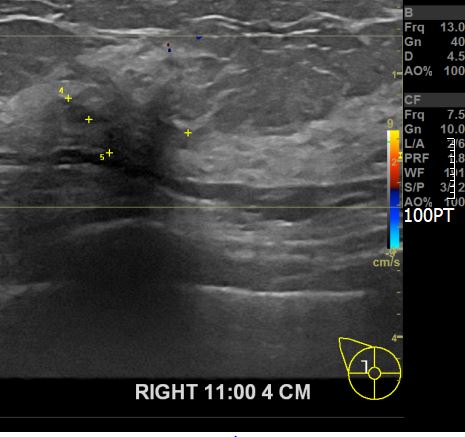

상기환자 외부검사상 이상소견으로 내원하신 50대 후반 여성분으로

우측 조직검사 시행해 상피내암으로 진단되었습니다.